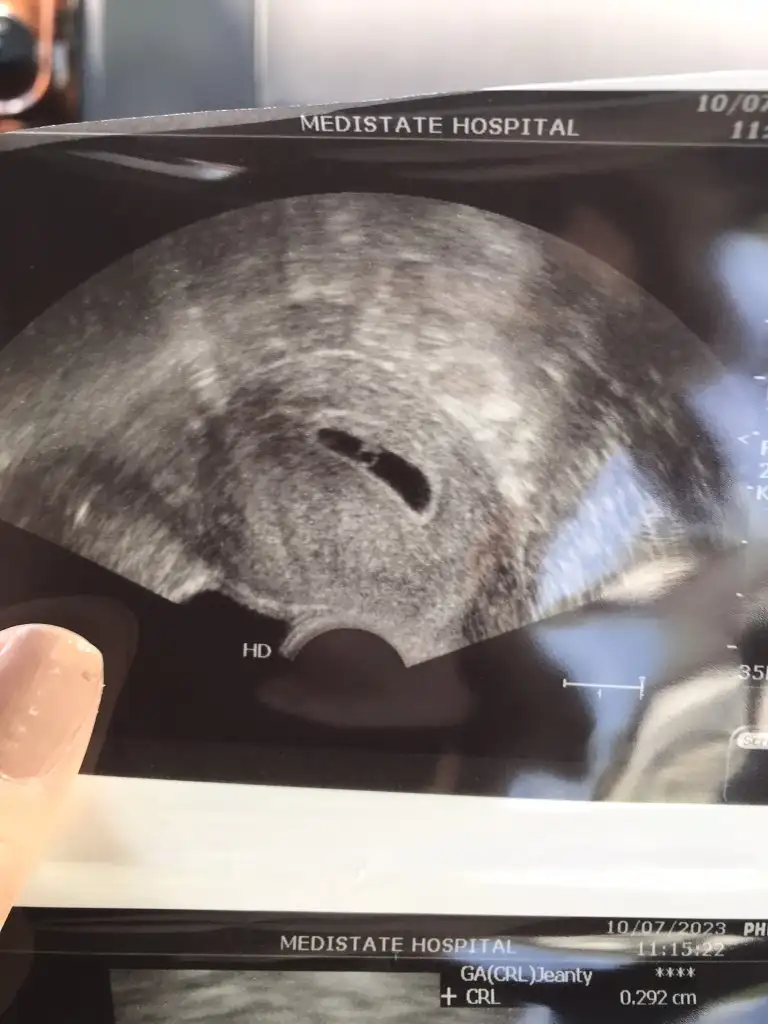

Herkese merhabaaİnsallah bende mart annesi olacağım, tüp bebekle ikinci denememde hamileyim çok şükürrr Sat 28mayıs ama transferi 17 haziranda olmuştum bizde hesaplamalar bazen kayabiliyor pazartesi doktora gittiğimde doktor 5+2 gibi demişti biz bebeğide yolk kesesini de gördük çok küçük olduğu için çok az da kalp atışı duyduk bugün artık 5+6yım diye düşünüyorum Ultrason fotoğrafıda 5+2den

Gittim bebiş 5mm olmuşSiz bugün gidecektiniz değil mi, inşallah güzel haberler bekliyoruz sizden

Gözünüz aydın çok sevindimGittim bebiş 5mm olmuşkalbi atıyo çok şükür, kalp atışını gösterdi ultrasonda, dinletmedi henüz erken diye sanırım. 6+2yle uyumlu büyüklüğü dedi. Son adetime göre bugün 6+3 üm o kadarcık farkedebilirmiş